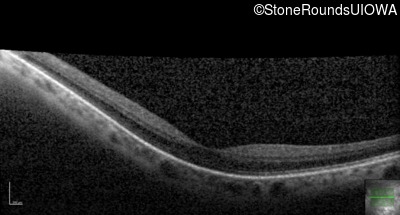

Age at visit: 41 years (Visit 2)

OD OS

This 41 year old woman was highly myopic as a child and experienced a rhegmatogenous retinal detachment OS at age 20.

Refraction OD:     -17.25 +1.00 x 93

Refraction OS:     -18.25 +3.50 x 56